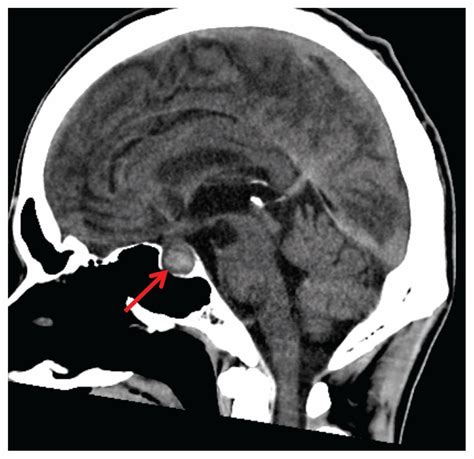

When patients present with symptoms related to hormonal dysregulation, a healthcare provider may order imaging to investigate the pituitary gland. This gland sits within a bony structure called the sella turcica. Because this area is quite intimate, standard brain scans may not always offer the resolution required to see micro-adenomas—very small tumors that can significantly affect hormone production. A dedicated pituitary gland MRI focuses specifically on this region, ensuring that even minute structural changes are identified.

For the most accurate results, a contrast agent (often gadolinium) is frequently used. This substance is injected intravenously to highlight blood flow and differentiate between healthy gland tissue and potential lesions or tumors. The contrast agent allows the radiologist to see the pituitary anatomy in vivid detail, making it easier to spot abnormalities that might otherwise be overlooked.

In some specialized centers, advanced MRI techniques are used for a more nuanced diagnosis. For example, dynamic contrast-enhanced MRI involves taking a series of images in rapid succession immediately after the contrast is injected. This allows radiologists to see exactly how a potential tumor "fills" with blood compared to healthy tissue, offering deeper insight into the nature of the lesion. These specialized approaches are highly beneficial when standard imaging results are inconclusive but clinical suspicion of a pituitary disorder remains high.